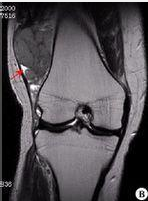

较常见的位置是靠近膝盖的大腿,但滑膜肉瘤也可以发生在其他关节附近,主要在手臂和腿部。它很少在一个联合中出现。